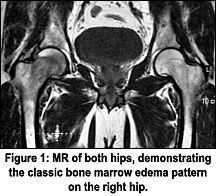

With a clinical presentation such as this, we generally need to be concerned with avascular necrosis (AVN), an inflammatory arthritis and an infection. There are other disorders that will give similar presentations, such as regional migratory osteoporosis and transient bone marrow edema syndrome (TBMES) - I would venture a guess that we may find these are just different forms of transient osteoporosis. For that matter, I prefer to describe transient osteoporosis as transient bone marrow edema, because the MR findings in both are essentially the same: hyperintense marrow signal in the femoral head and neck on the T2-weighted images.

Occasionally, AVN may manifest as a diffuse area of decreased signal on T1-weighted images and increased signal on T2-weighted images involving the femoral head, neck, and occasionally, the intertrochanteric femur. This has been termed the "bone marrow edema" pattern on MR imaging, since the signal intensities are compatible with increased free-water content. This is the classic pattern attributed to transient osteoporosis and TBMES. If the lesion is truly an AVN, it will change in its appearance with follow-up studies, demonstrating the bone marrow edema pattern evolving into focal patterns entirely characteristic of AVN.

The MR pattern of bone marrow edema is not specific. The differential diagnosis includes AVN, transient osteoporosis, bone bruise, infiltrative disease, and transient bone marrow edema syndrome. Although the clinical history can be helpful in distinguishing between these entities (e.g., a history of trauma as the etiology of a bone bruise), in other cases, a definite diagnosis can only be made based on the time course of the imaging and clinical findings.